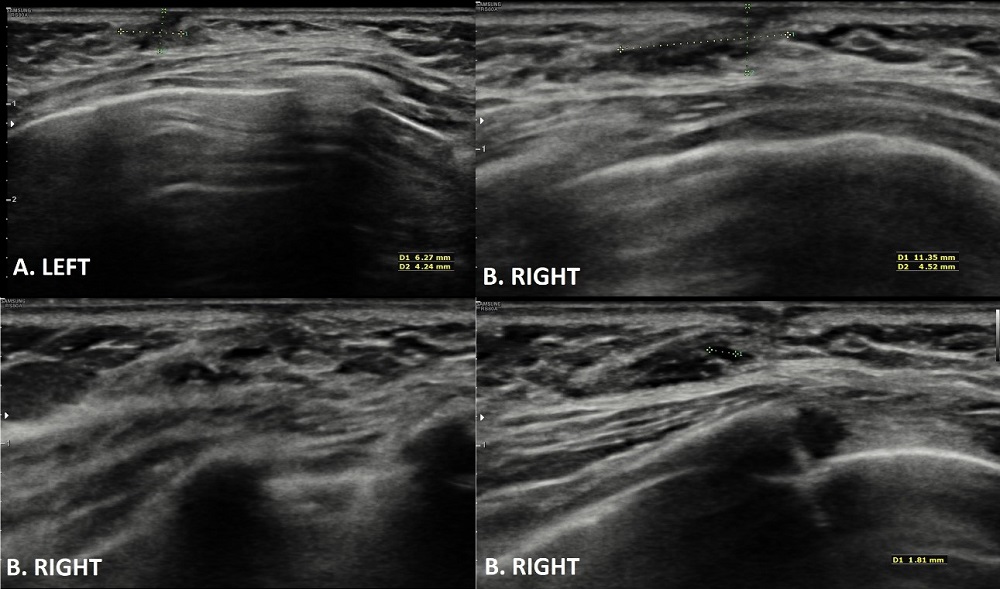

Ante la ausencia de otros hallazgos patológicos en la exploración que sugieran alteración endocrinológica, no se realiza analítica hormonal. Por el mismo motivo, no se observan signos de patología infecciosa (fiebre, eritema, secreción purulenta, etc.), no se solicitan cultivos de la secreción. Si se realiza citología de la secreción de la mama derecha en la que se describe un extendido de fondo hemorrágico con elementos inflamatorios y algunas células espumosas sin observarse células atípicas (Fig. 1). Asimismo, se solicita una ecografía mamaria (Fig. 2) que objetiva imágenes compatibles con ginecomastia bilateral asimétrica mayor en el lado derecho y discreta ectasia ductal derecha. Describe imágenes hipoecogénicas de contorno lobulado en región retroareolar de ambas mamas en relación con parénquima mamario. En la mama izquierda de 6×4×3 mm y en la derecha de 11×4×9 mm.

| Figura 2. Ecografía mamaria. A. Mama izquierda. B. Mama derecha. Ambas mamas muestran imágenes hipoecogénicas retroareolares compatibles con ectasia ductal mamaria |

|---|